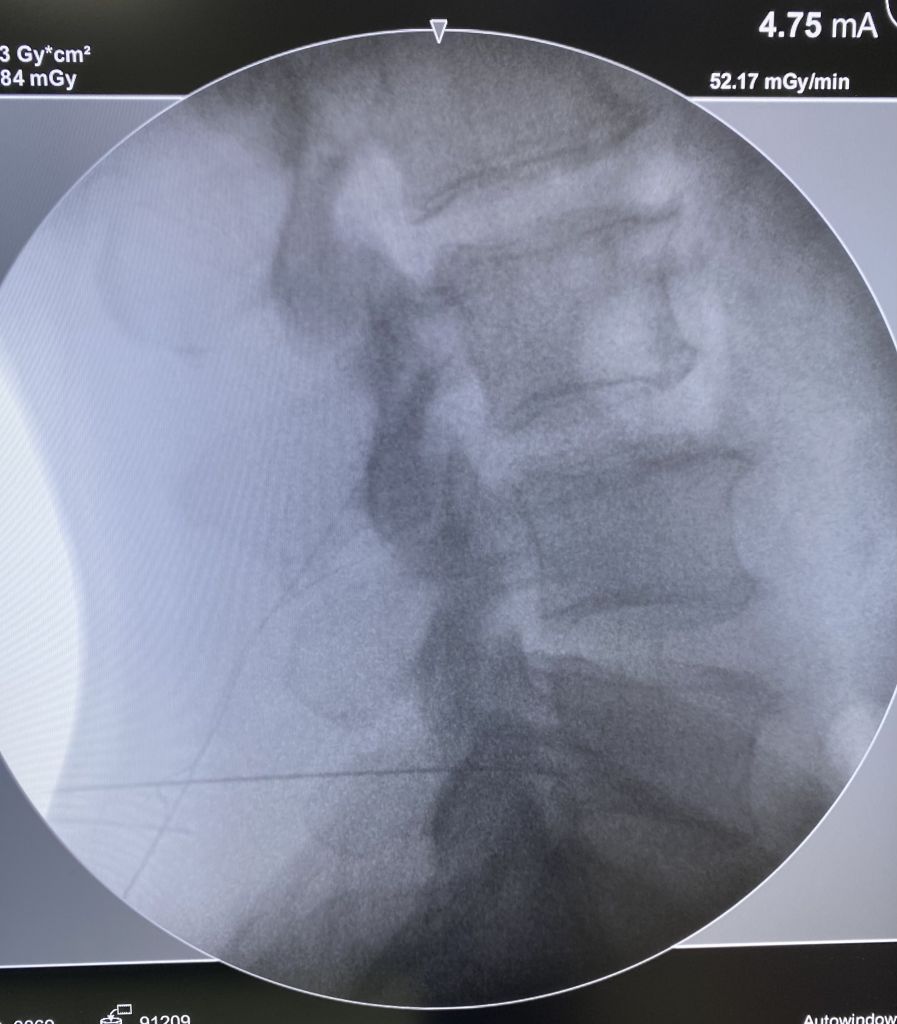

A infiltração da coluna, também chamada de bloqueio da coluna, denervação facetária ou bloqueio foraminal é um procedimento realizado pelo especialista em coluna que permite tratar a dor da hérnia de disco e outros problemas na região sem a necessidade de realização de cirurgia aberta. Ortopedista de coluna, especialista em coluna, infiltração da coluna

Geralmente, o procedimento dura menos de 1 hora e o paciente pode ter alta poucas horas depois. Não é necessária anestesia geral, apenas sedação leve para conforto e anestesia local. Na maioria das vezes, a melhora é imediata e pode persistir por vários meses. especialista em coluna,